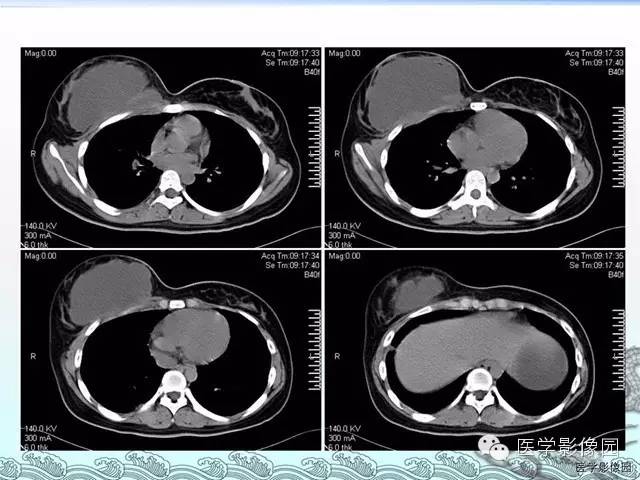

胸壁结核1例影像表现

【病例】胸壁结核1例影像表现